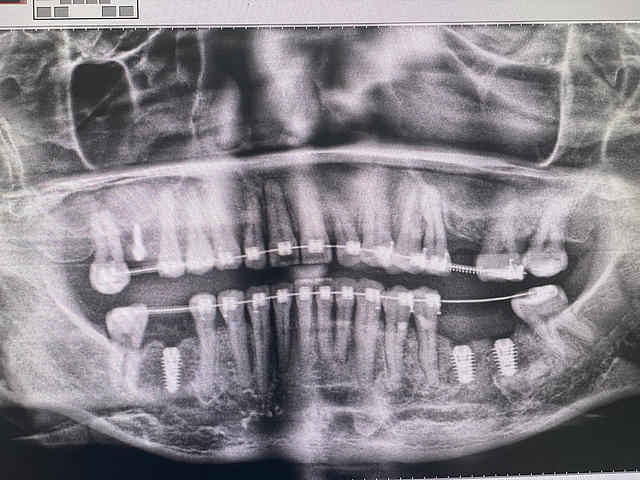

Понравилась знакомая и родная упаковка имплантата. Сам имплантат вариативен по размерам и имеет выраженную резьбу. На верхней челюсти стабилизация имплантата не составила труда, даже небольшой переизбыток торка. Хирургический набор тоже напомнил стандартный набор импро, интуитивно понятное использование сверел. Заглушка в комплекте тоже некий плюс в копилку импро.Пациент: Г., женщина, 43 года, пациент на ортодонтическом лечении

Ранее зубы 46,36,37 удалены по поводу осложненного кариеса. На КЛКТ снимке костное предложение позволяет установить имплантаты 5,5х9,5 в позиции 36 и 37 Зубов. Справа установлен Эниридж 4,5х10.На нижней челюсти установка имплантата прошла по другому протоколу, так как плотность кости выше, чем на верхней. Хирургический набор позволил с легкостью установить имплантаты, с хорошим торком. Далее по плану принято решение о пластике мягких тканей вокруг имплантатов с установкой ФДМ. И протезирование временное, затем постоянное.